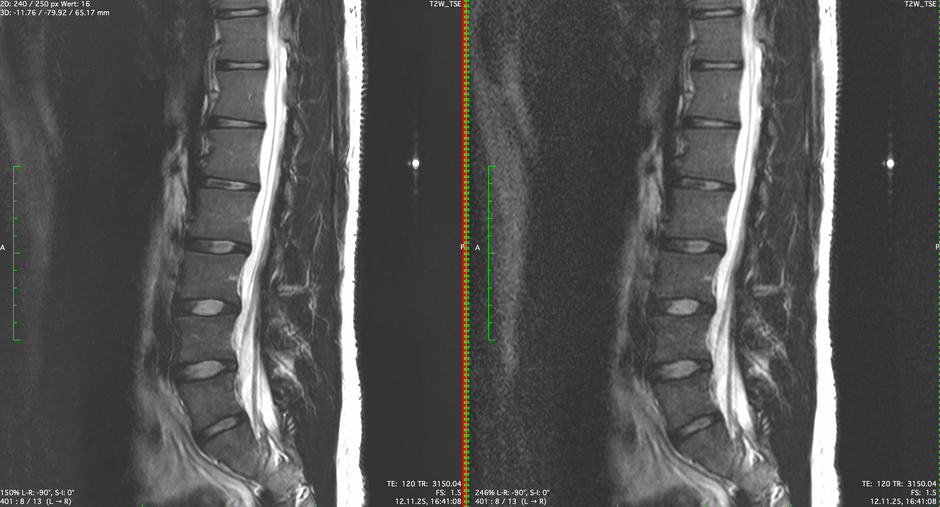

MRT der LWS mit künstlicher Intelligenz

Schärferes Bild mit besserer Auflösung und mehr Detailsschärfe.

Geringeres Bildrauschen.

MRT der LWS ohne künstliche Intelligenz

Bild mit geringerer Auflösung .

Deutliches Bildrauschen.